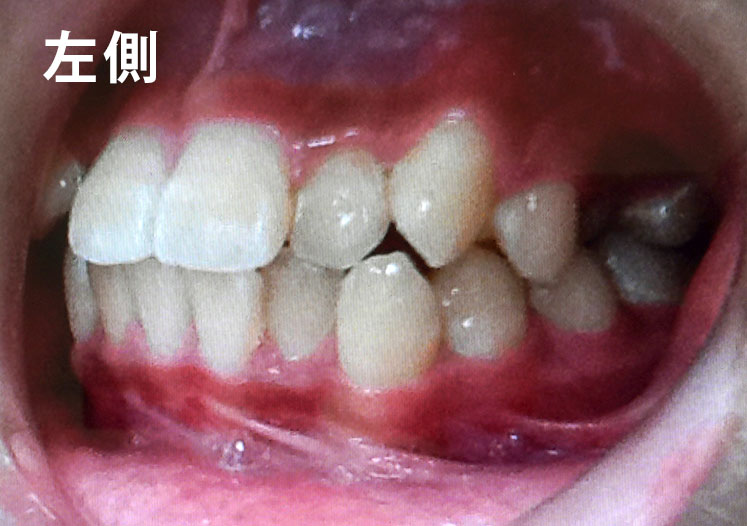

• 症例2

矯正bofore

矯正種類 ワイヤー矯正

症例 上下額叢生

治療期間 2021年12月〜2024年10月

性別/年代 男 13歳

治療費 748,000円

コメント

適切な時期に治療が開始できたので、歯並びだけでなく顎や顔貌も理想的に成長しました。歯磨きもしっかりできるようになりました。